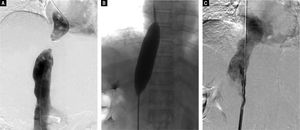

Preoperative contrast-enhanced CT revealed marked atrophy of right lobe of the liver and compensatory enlargement of left lobe, no liver mass, and splenomegaly. Vascular findings were a membranous obstruction of the IVC with dilatation of the upper lumbar tributaries and hemiazygous/azygous veins (Figure 1A); a whole-course obstruction of the right HV; a membranous obstruction of the middle HV and left HV at the orifice of the HV (Figure 1B); and a dilated phrenic vein and pericardial vein, draining blood from the middle HV and the left HV to the superior vena cava. Portal venous-phase images revealed a side-to-side anastomosis of 2 mm diameter between the PV and IVC (Figure 1C). The splenic and superior mesenteric veins were normally oriented and joined to form the main PV. These results were consistent with those of abdominal Doppler ultrasound (Figure 2). The diagnosis of type II Abernethy malformation and BCS was made.

Preoperative CT images. A. CT-angiography reveals a membranous obstruction of the intrahepatic IVC (arrow). B. Axial porta venous phase CT scan reveals that the right HV cannot be visualized; the co-orifice of the middle HV and left HV have a membranous obstruction; and the azygos and hemiazygos veins are markedly dilated (arrow). C. Axial porta venous phase CT scan reveals a side-to-side anastomosis (arrow) between the portal vein and IVC, a finding compatible with type II Abernethy malformation.